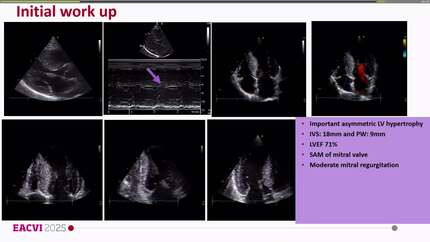

From STEMI to HCM: diagnostic and therapeutic insights in a 54-year-old patient treated with Mavacamten